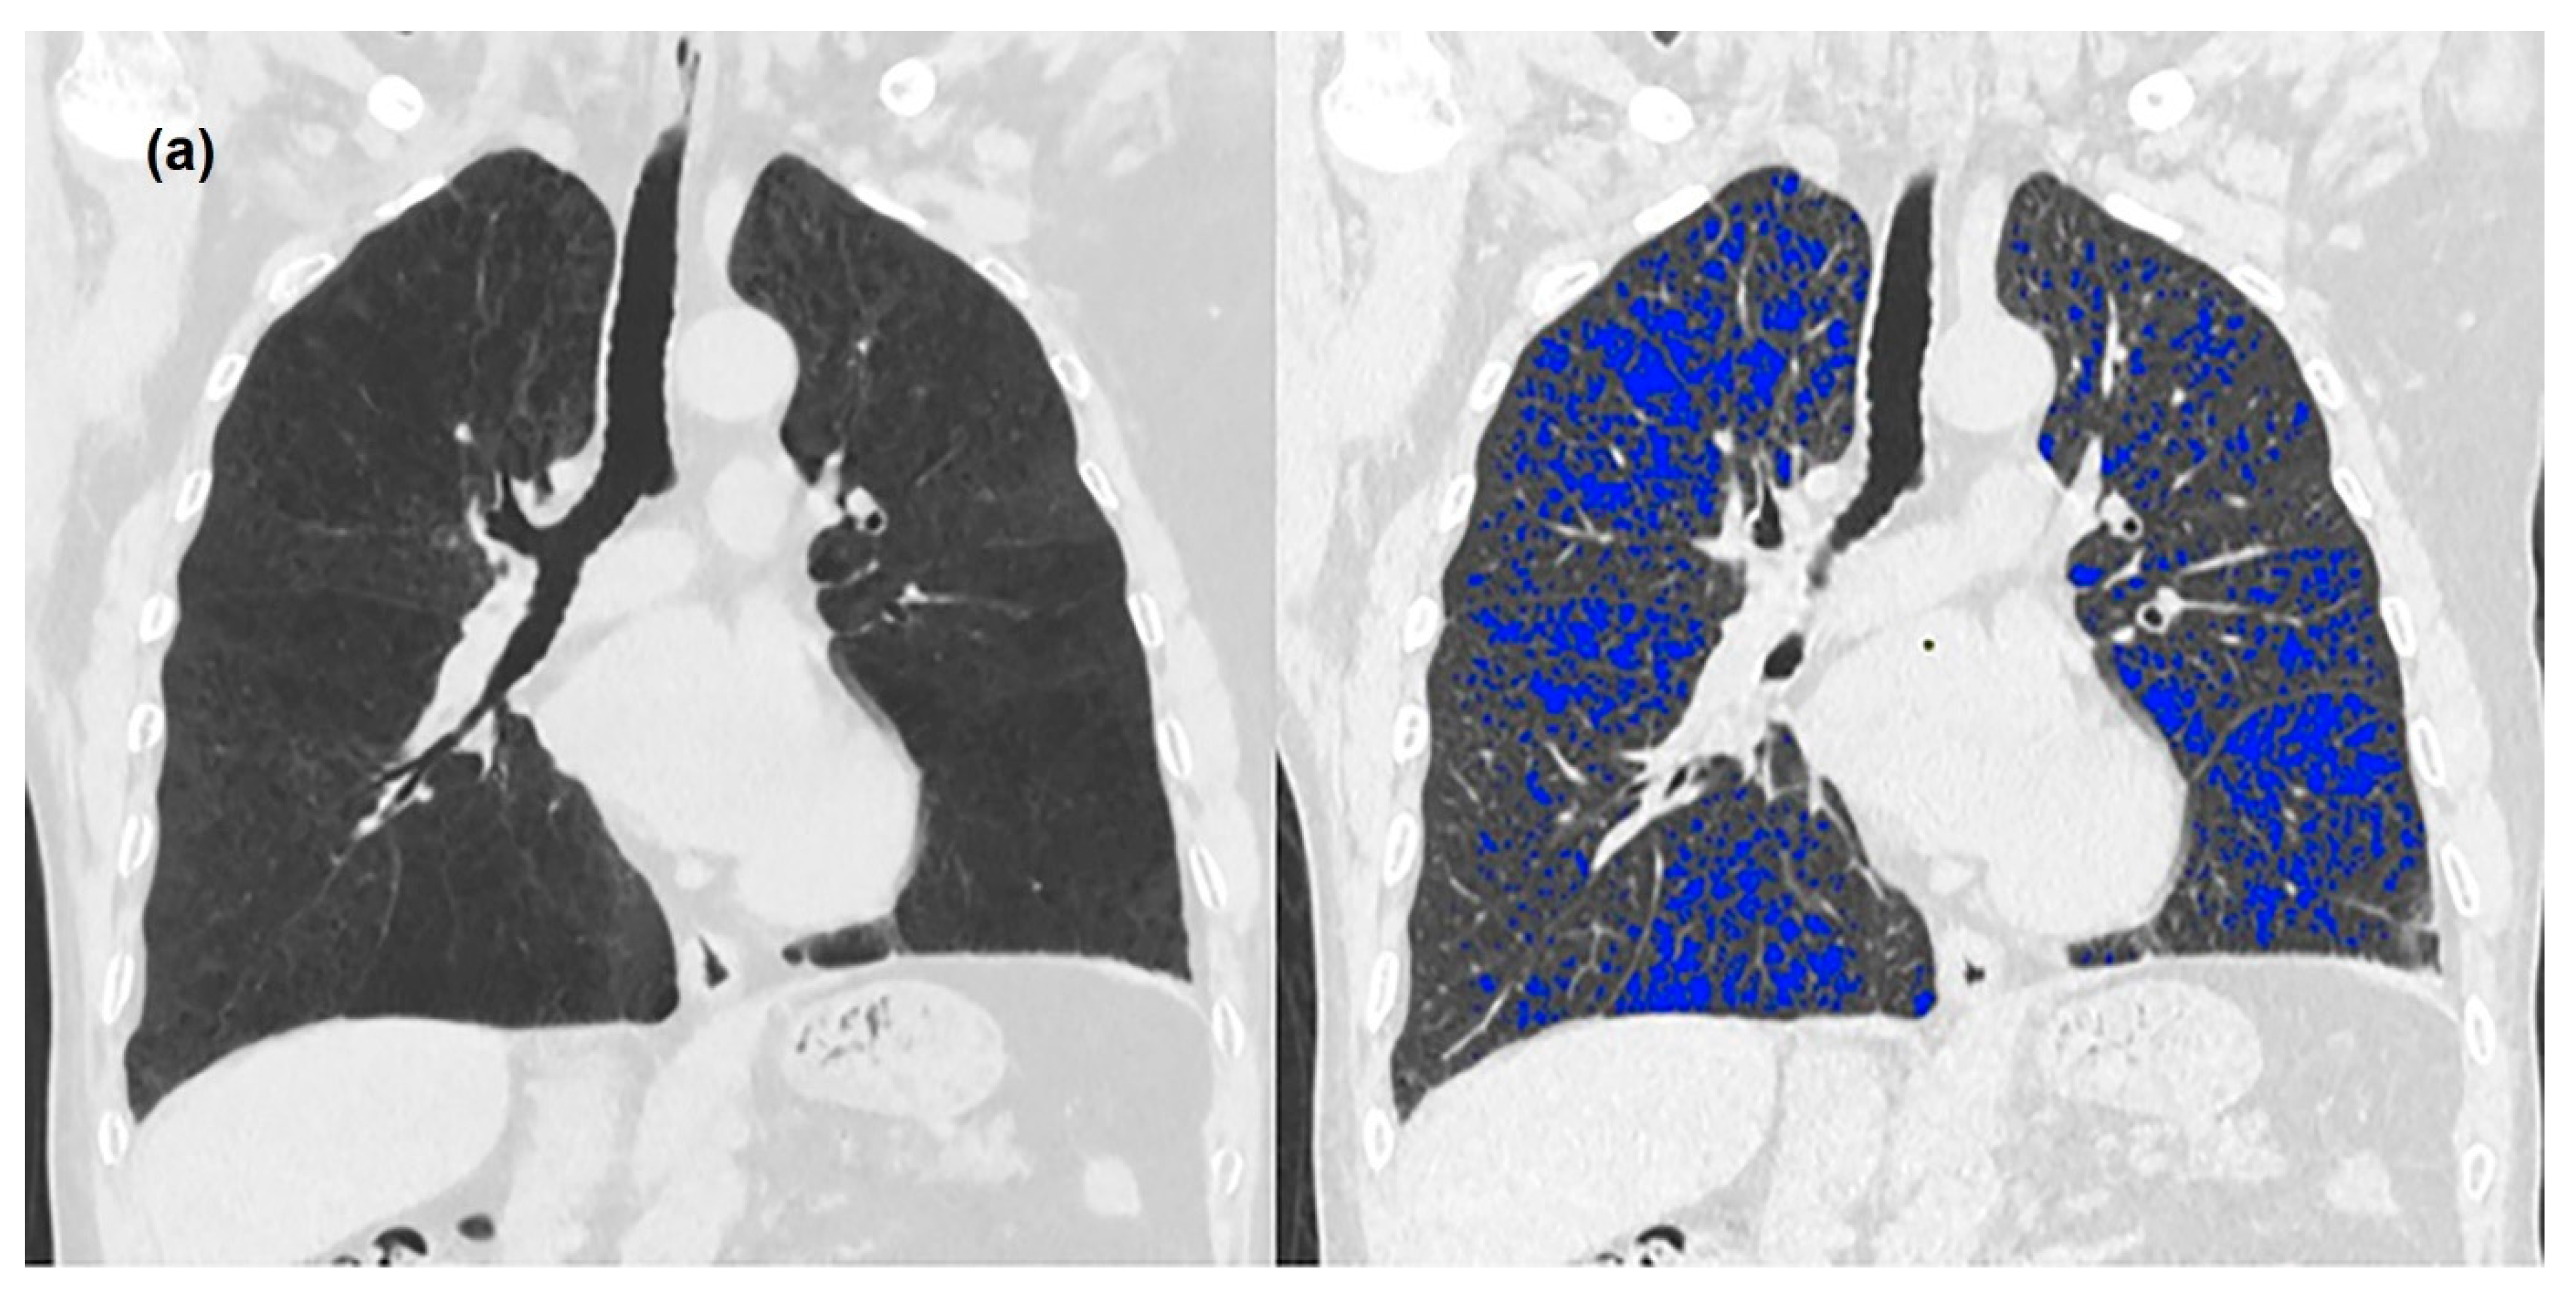

2.3. Image Analysis

3. Results

3.2. Quantitative Measurements of Standard-Dose and Ultra-Low-Dose CT